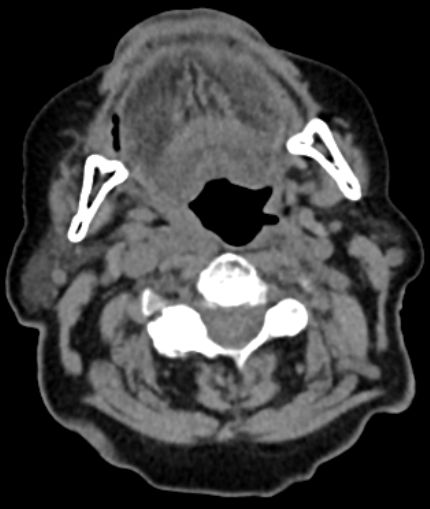

63-jähriger Mann mit Leberzirrhose und ACI-Stenose.

Es besteht ein Hypopharynx - Karzinom und ein Weichgaumenkarzinom mit Übergang auf den harten Gaumen.![]() | |||||||||||||||||